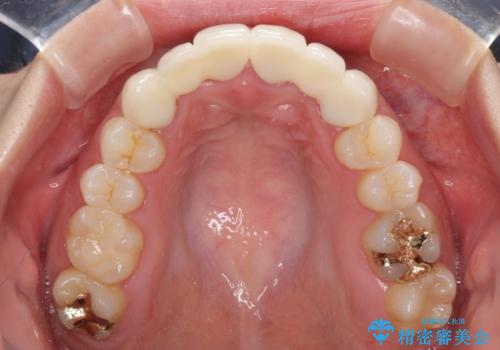

矯正治療後に前歯をセラミックブリッジに、奥の銀歯はセラミックインレーやPGAインレー(ゴールドインレー)にて補綴・修復治療を行うこととしました。

矯正治療により下顎前歯を整列させたため、上顎前歯のセラミックブリッジを補綴することで口元を少し下げることができました。

ヒトの目線がいつも口元に向けられているように感じることがなくなり、患者様には大変満足していただきました。